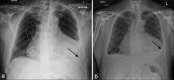

Acute pericarditis and cardiac tamponade after COVID-19 vaccination